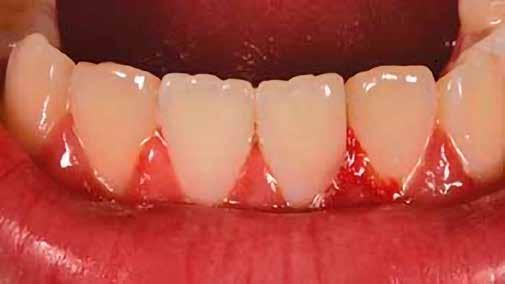

2. ábra: A páciens egy nem megfelelő I. osztályú ezüstamalgám töméssel és II. osztályú szuvasodással jelentkezett. A fog izolálása kofferdám alkalmazásával történt.

3. ábra: A preparálás, a bondozás és a kompozit felvitele után. (Megjegyzés: némi kompozit túlfolyás látható a mesiális doboz axiális falain).

4. ábra: A durva finírozás után a restauráció pereme sima és anatómiailag is megfelelő.